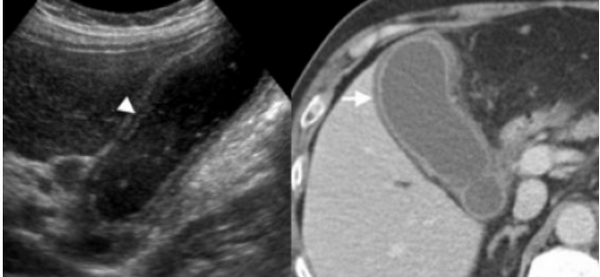

(Левый) На продольном косом УЗ срезе у пациента с острым веска менным холециститом с гангреной, перенесшего трансплантацию легкого, визуализируется растянутый желчный пузырь, содержащий вязкий сладж. Стенка желчного пузыря утолщена, ее контур имеет дефекты.

(Правый) На продольном косом срезе у того же пациента определяется гиперемия перипузырной зоны, признаки кровотока в некротизированной стенке отсутствуют.